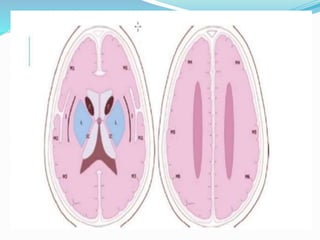

 The Alberta Stroke Programe Early CT Score

(ASPECTS) is a 10-point quantitative topographic CT

scan score used in patients with middle cerebral

artery (MCA) stroke.

 Segmental assessment of MCA territory is made and 1

point is removed from the initial score of 10 if there is

evidence of infarction in that region.

 caudate

 putamen

 internal capsule

 insular cortex

 M1: "anterior MCA cortex," corresponding to frontal

operculum

 M2: "MCA cortex lateral to insular ribbon"

corresponding to anterior temporal lobe

 M3: "posterior MCA cortex" corresponding to posterior

temporal lobe

• M4: "anterior MCA territory immediately superior to

M1"

• M5: "lateral MCA territory immediately superior to

M2"

• M6: "posterior MCA territory immediately superior to

M3"

 (M1 to M3 are at the level of the basal ganglia and M4

to M6 are at the level of the ventricles immediately

above the basal ganglia)

 An ASPECTS score less than or equal to 7 predicts

worse functional outcome at 3 months as well as

symptomatic haemorrhage.